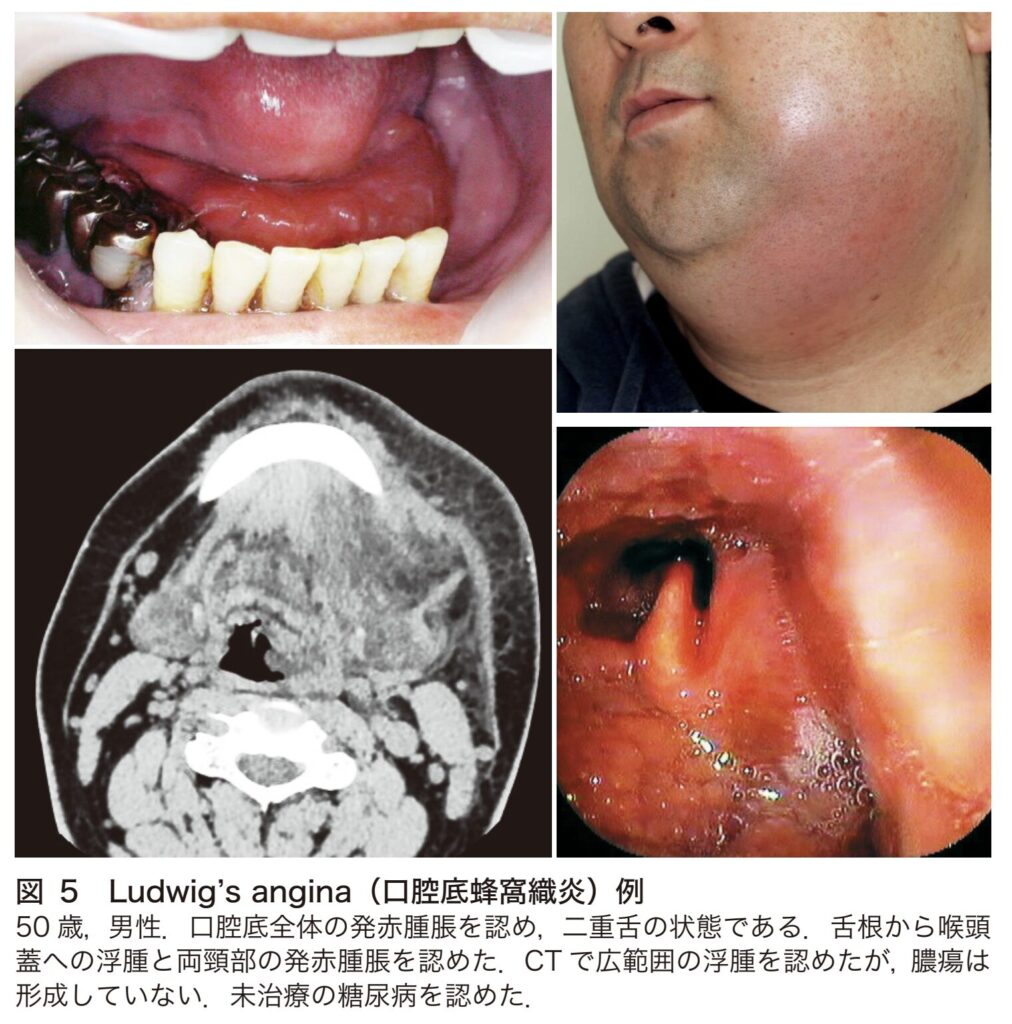

Ludwig’s angina(口腔底蜂窩織炎)

Ludwig’s angina(ルートヴィヒ・アンギナ/口腔底蜂窩織炎)は、口腔底から広範囲に炎症が波及し、両側の頸部蜂窩織炎に至る、急速に広がる壊死性の感染症です。見逃すと窒息に至るおそれのある重篤な疾患です。

原因

- 53~96%が歯性感染を契機として発症します。

症状

- 明白な膿はほとんど形成しませんが、短時間のうちに炎症が拡大します。両側口腔底が腫れ上がることで、舌が押し上げられて「二重舌」の状態になります。さらに、咀嚼筋や喉頭へ炎症が波及すると、開口障害、嚥下障害、流涎、構音障害などが生じます。

- 舌根部の腫大や咽喉頭浮腫をきたしやすく、急速な気道閉塞を引き起こす危険性があります。

- 炎症が副咽頭間隙から縦隔へと連続して進展すると、悪寒戦慄を伴う高熱や敗血症を併発し、直接生命に危険を及ぼします。